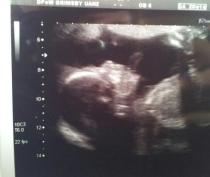

Just wanted to share my scan picture with you. Can't believe how clearly you can see the shape of her face. The sonographer did a close up of her face too for us, we could even see the shape of her lips, amazing!

That scan is so clear. Amazing!